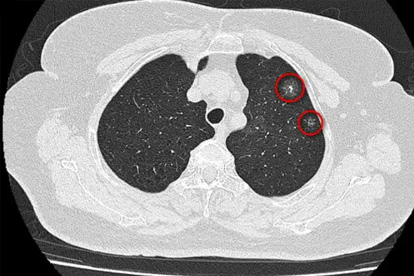

1、在马路边快走

机动车尾气中含有大量PM2.5和苯并芘等致癌物。这些颗粒会直接沉积在肺泡,建议选择公园或小区内部道路。